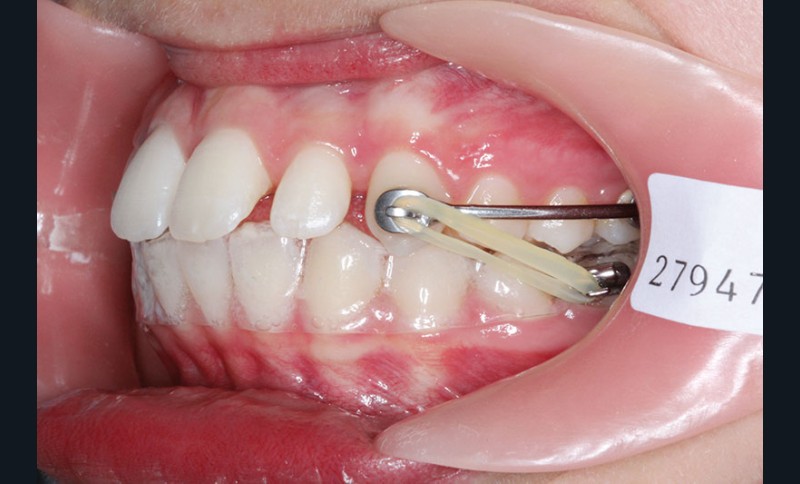

Il a été décidé de mettre en place un système de correction de la classe II “Motion Classe II Carriere” composé de bras latéraux reliant canine et molaire et d’élastiques de classe II ancrés sur des tubes molaires sur 36 et 46 et une gouttière thermoformée portée en permanence. sAprès dérotation des 16 et 26, recul des secteurs latéraux et libération de la croissance mandibulaire nous mettrons en place un système multiattache autoligaturant passif Carriere SLX 022×028 avec la séquence d’arcs suivante :

1re phase : le Motion Appliance Carriere

Afin d’obtenir la correction de la classe II, nous avons fait porter pendant 3 mois une mécanique d’élastiques intermaxillaires, jour et nuit, avec la séquence suivante (fig. 4):

1er mois : élastiques 6oz. ¼”

2e mois et mois suivants : 8 oz. 3/16”